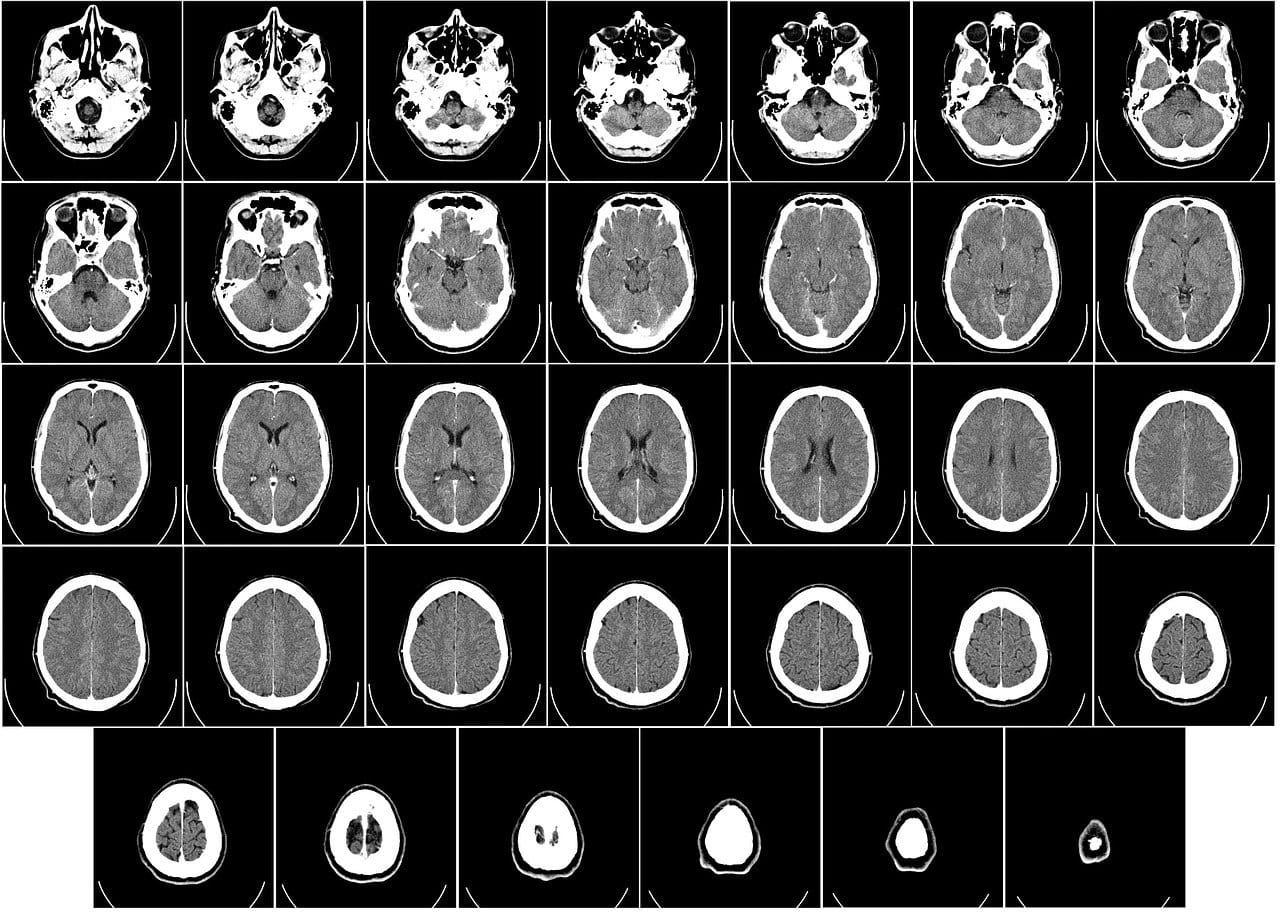

AMT-130 uses an adeno-associated virus or AAV, a harmless virus that's easily engineered to deliver genetic material of our choosing. The hard part is getting it where it needs to go: the striatum, a region deep inside the brain that's involved in motor skills and cognition, and that suffers some of the most severe damage from Huntington's.

To deliver it, surgeons use a technique called stereotactic surgery. Surgeons use live MRI images to guide probes into the patient's brain, where they release the AAV agent in precisely the right place. Once it enters brain cells, it delivers its cargo.